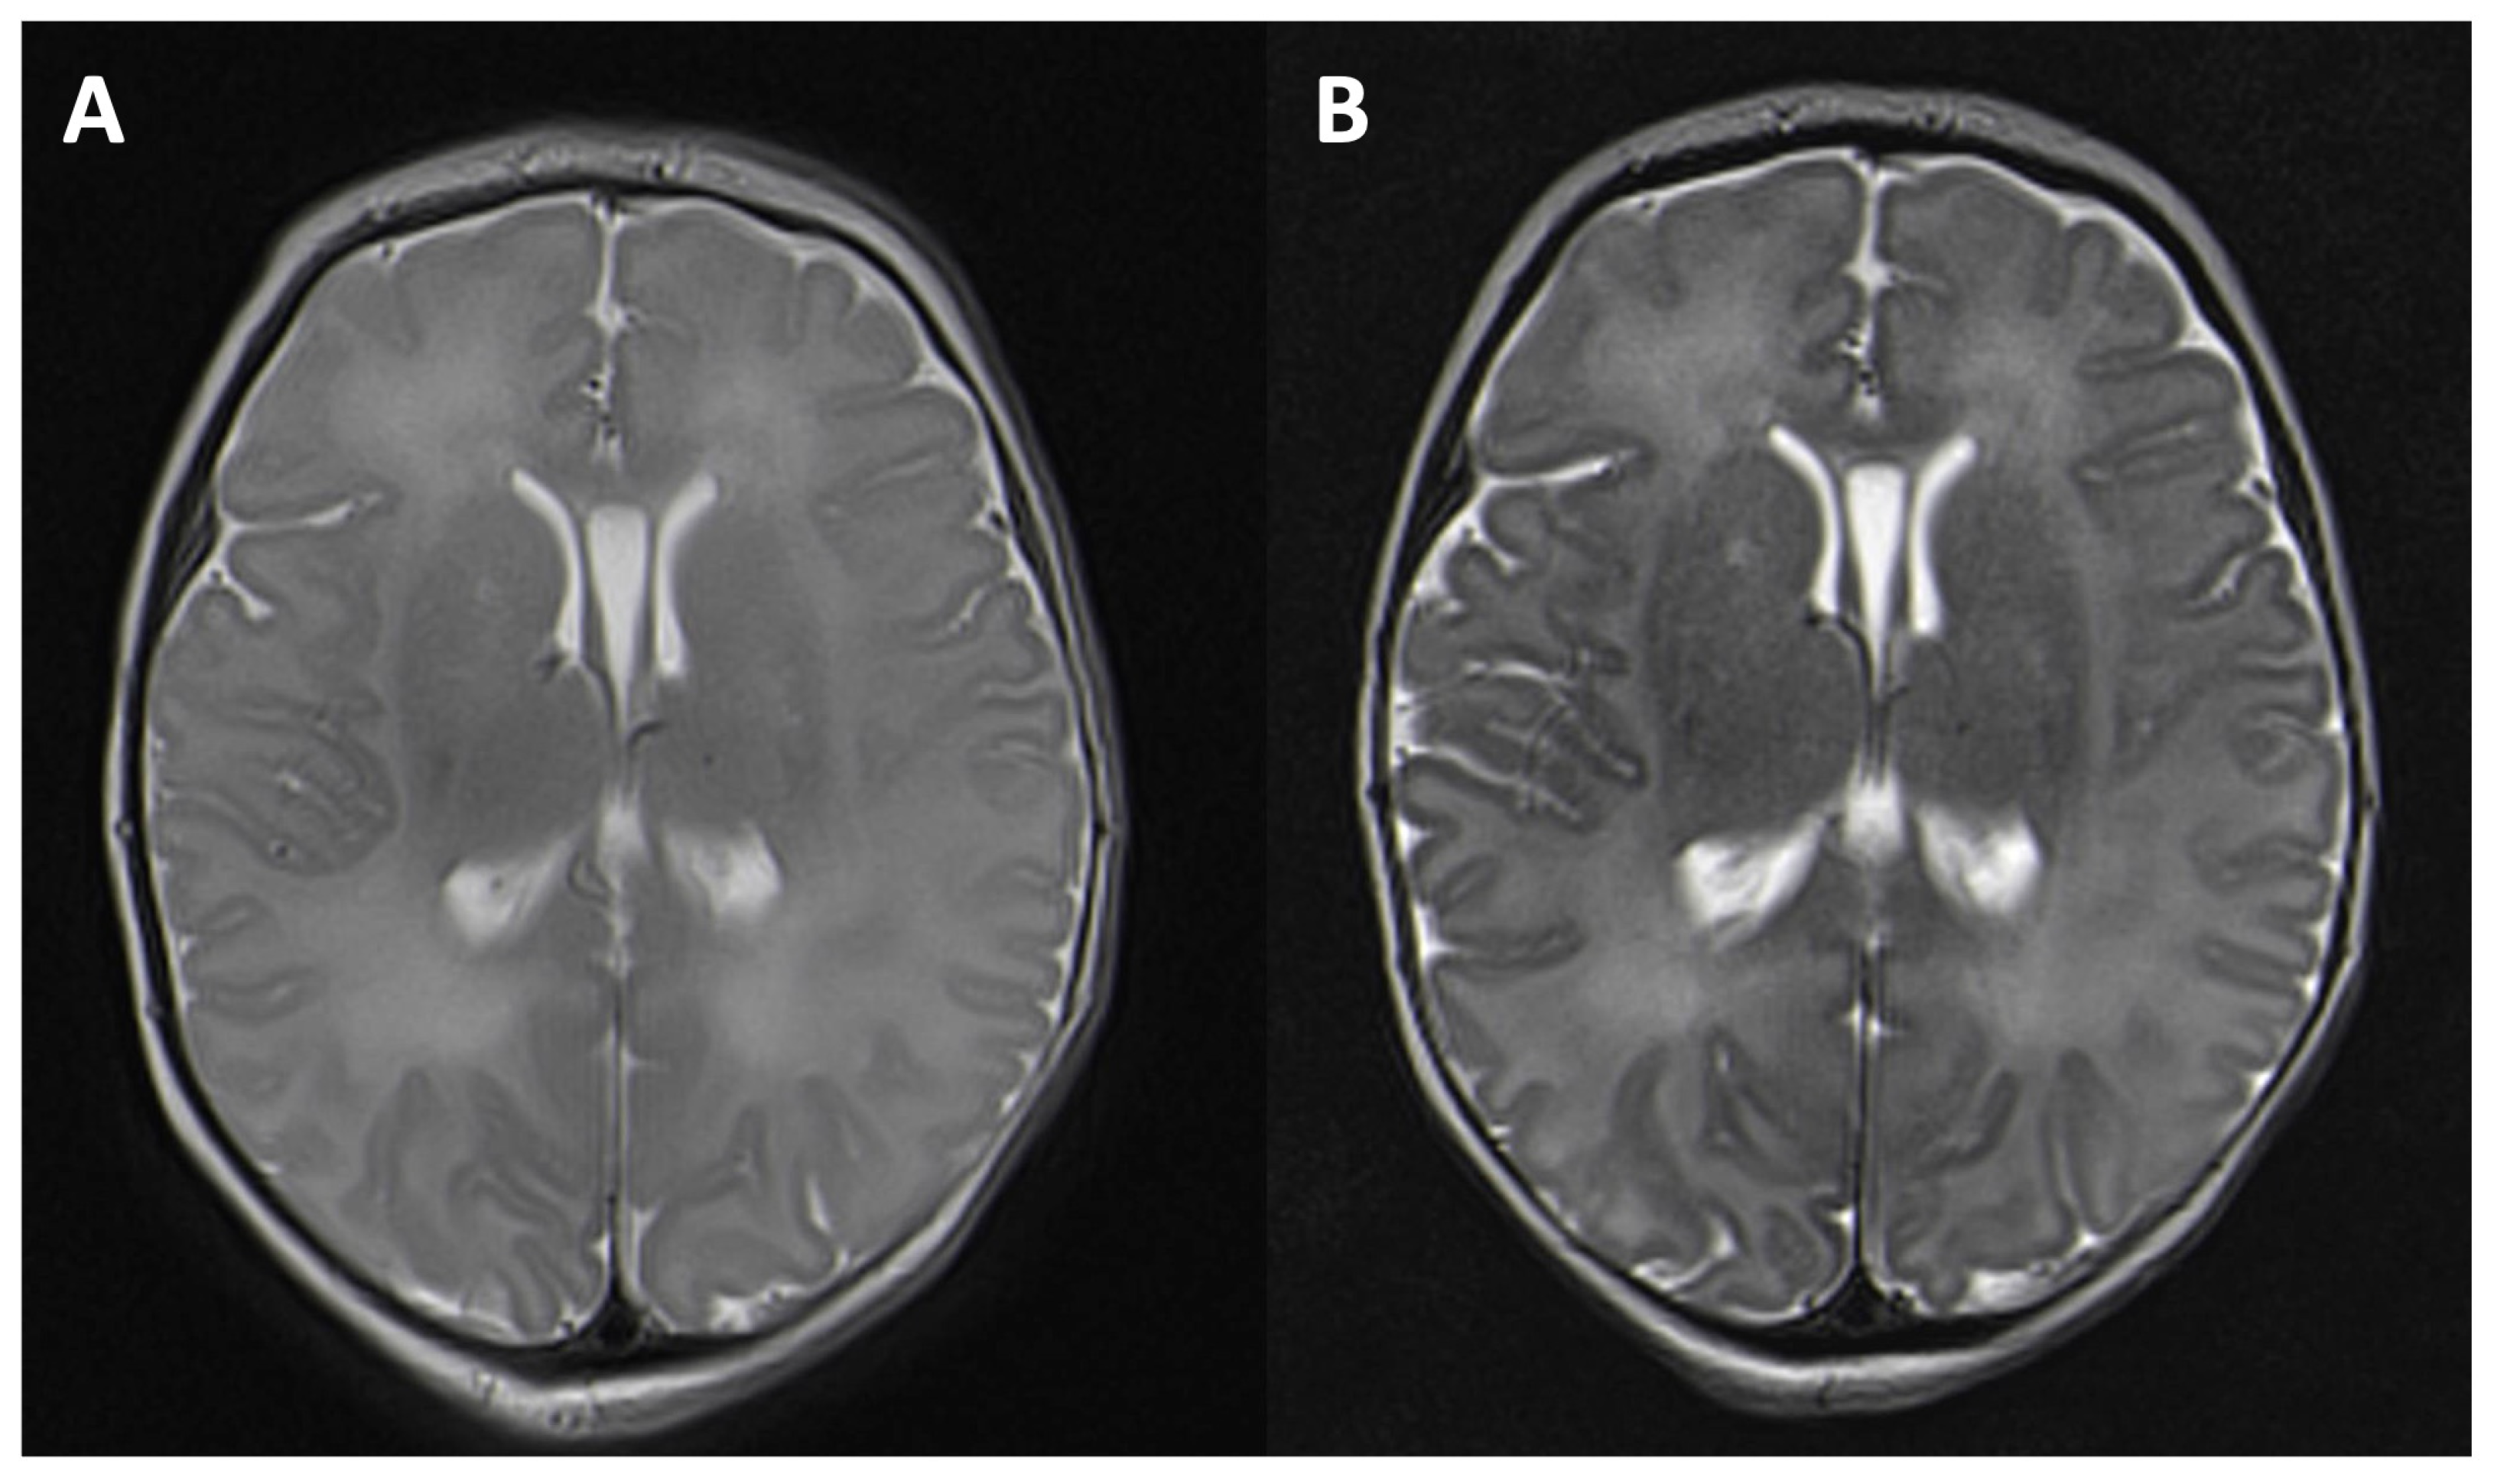

Figure 1.

T2-weighted image in an axial orientation of a six-day-old girl after asphyxia. A higher grey–white matter contrast can be seen with a longer echo time of 203 ms, repetition time of 5500 (B) than with a medium echo time of 113 ms, repetition time of 6950 (A).